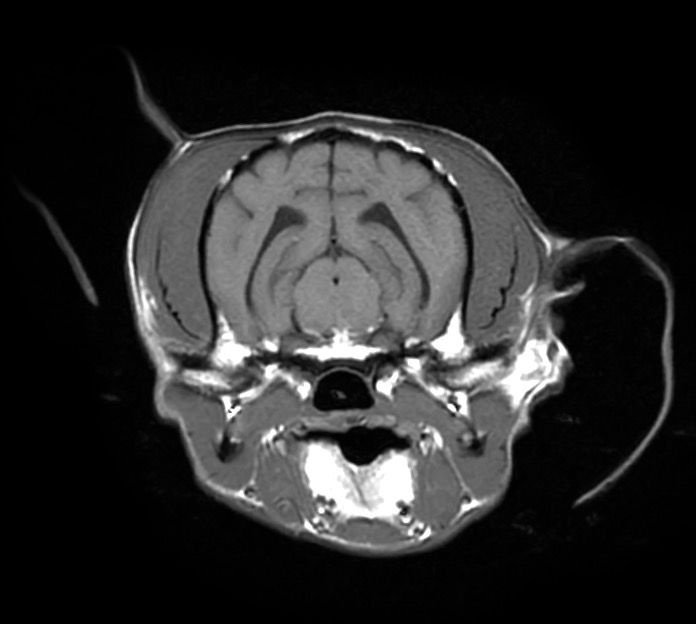

治療開始2週間後に実施した頭部MRI再検査では、脳の浮腫といった脳圧亢進所見、大脳後頭葉領域の炎症所見がすべて改善し、 わんちゃん自身もふらつきや眼振は無くなり、元気や食欲といった一般状態も極めて良好でした。

脳炎は治療をストップすると再発する恐れがあるため現在も治療継続中ではありますが、

早期診断→早期治療を行えたため、現在も良好な経過をたどっています。